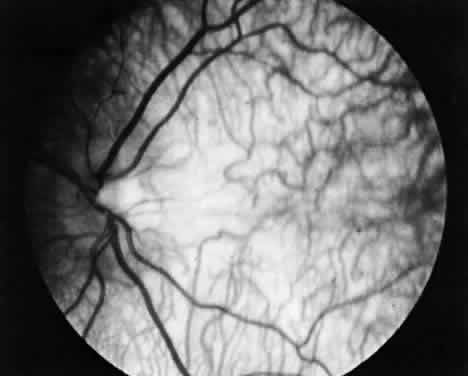

The lens in homocystinuria is much more mobile than in the Marfan syndrome. This may be related to the clinical observation of progressive irregularity of the zonular fibers and the appearance of a fringe of white zonular remnants at the equator of the lens and on the surface of the ciliary body (Fig. 1).12,13 Henkind and Ashton first reported histopathologically the ocular findings in four eyes of three homocystinuric patients. They found the zonular fibers to be deficient adjacent to the lens. These zonules had recoiled to the surface of the ciliary body and were matted and retracted into a feltwork that fused with a greatly thickened basement membrane of the nonpigmented epithelium. The greatly thickened basement membrane overlying the ciliary body in homocystinuria has subsequently been shown by electron microscopy to be composed of degenerate zonular material.14 In addition, Ramsey and coworkers noted that the degree of zonular abnormality was related to age: the younger the patient, the more normal-appearing zonular fragments composed of oriented filaments that could be identified.14 The zonular fibers are composed of glycoproteins with a high concentration of cysteine, which may explain their susceptibility to abnormal function in homocystinuria.15,16

Fig. 1. Inferior dislocation of the lens in a homocystinuric patient. Note the absence of most zonular fibers. (Nelson LB, Maumenee IH: Ectopia lentis. Surv Ophthalmol 27:143, 1982)